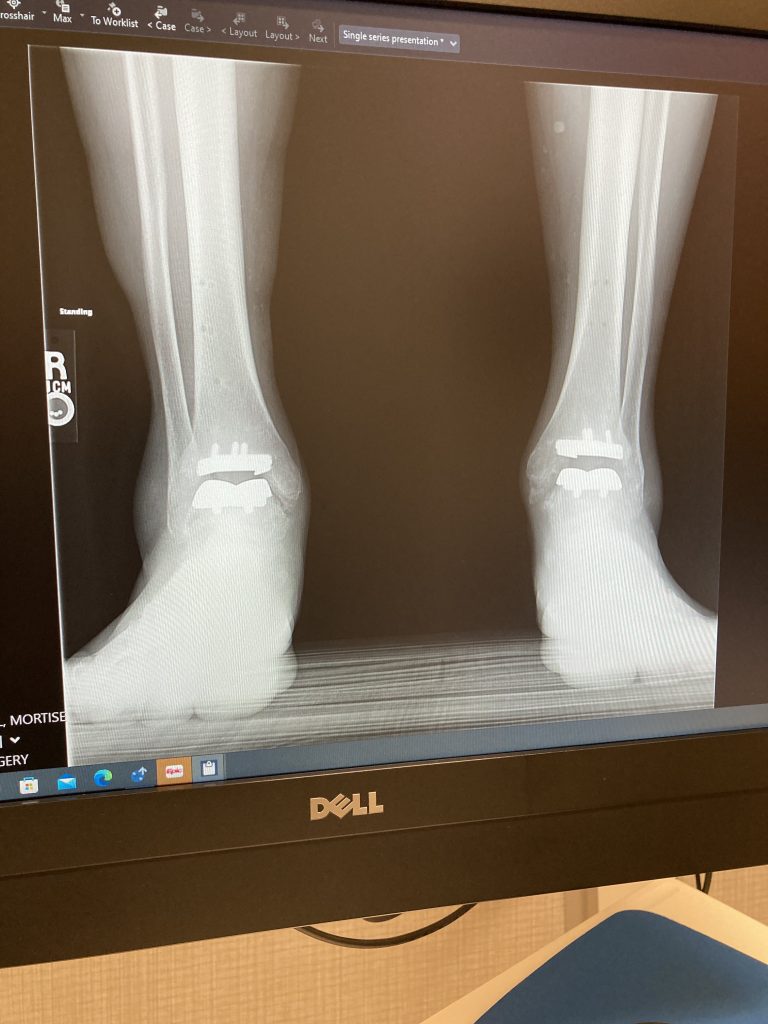

Ankle Replacement (Ankle Arthroplasty)

After 10 years of pain and inability to walk without stopping frequently I was referred to HSS for evaluation. The result was total ankle replacement (TAR) surgery, which was recommended for both ankles. The surgeries were 6 months apart and the treatment and care provided by Dr. Cody, HSS, and Stamford Hospital were beyond fantastic. Follow-up has been thorough and ongoing. I'm walking again! Thank you HSS!